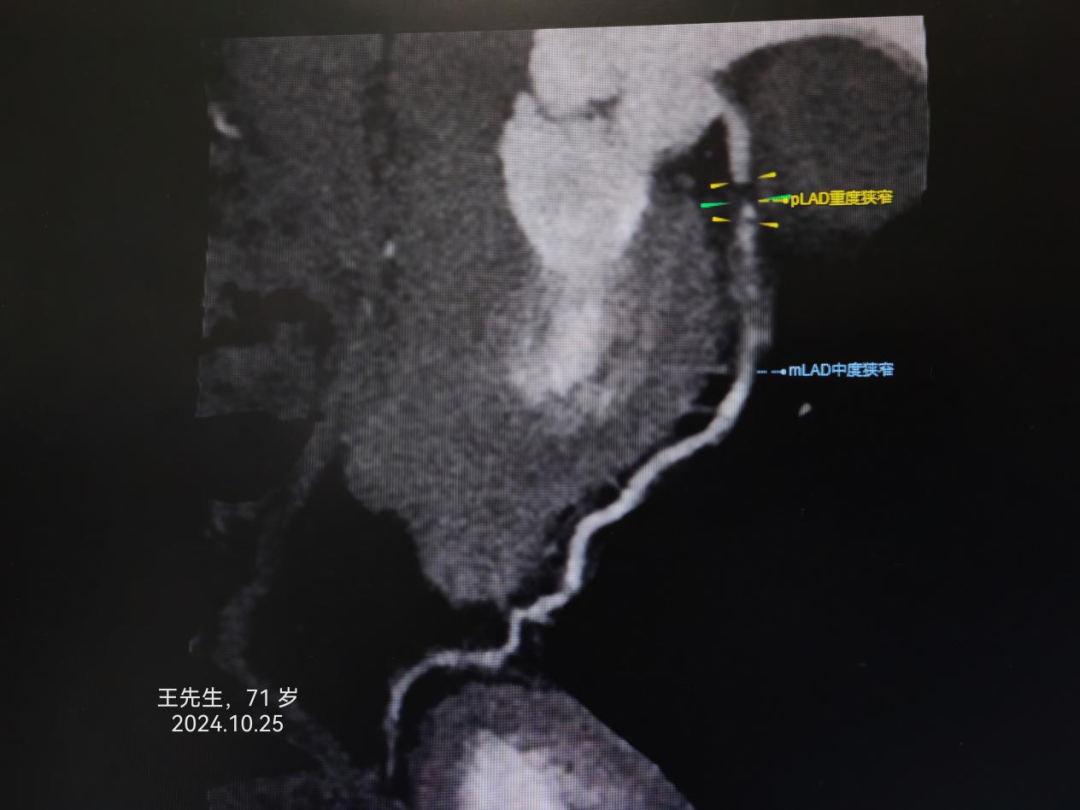

病例2:王先生,71岁,诊断“急性心肌梗死”。

寿光和信医院目前引进的中国联影640排高端螺旋CT天河960+,对冠脉成像有独特的优势,可无限制心脏成像,单心跳-高心率冠脉成像、单心跳-严重心律不齐、单心跳-自由呼吸扫描,成像效果极佳,与冠脉造影结果差距极小,并且检查时间3-5分钟、较之前缩短75%。部分冠脉CTA、冠脉造影结果对比如下: